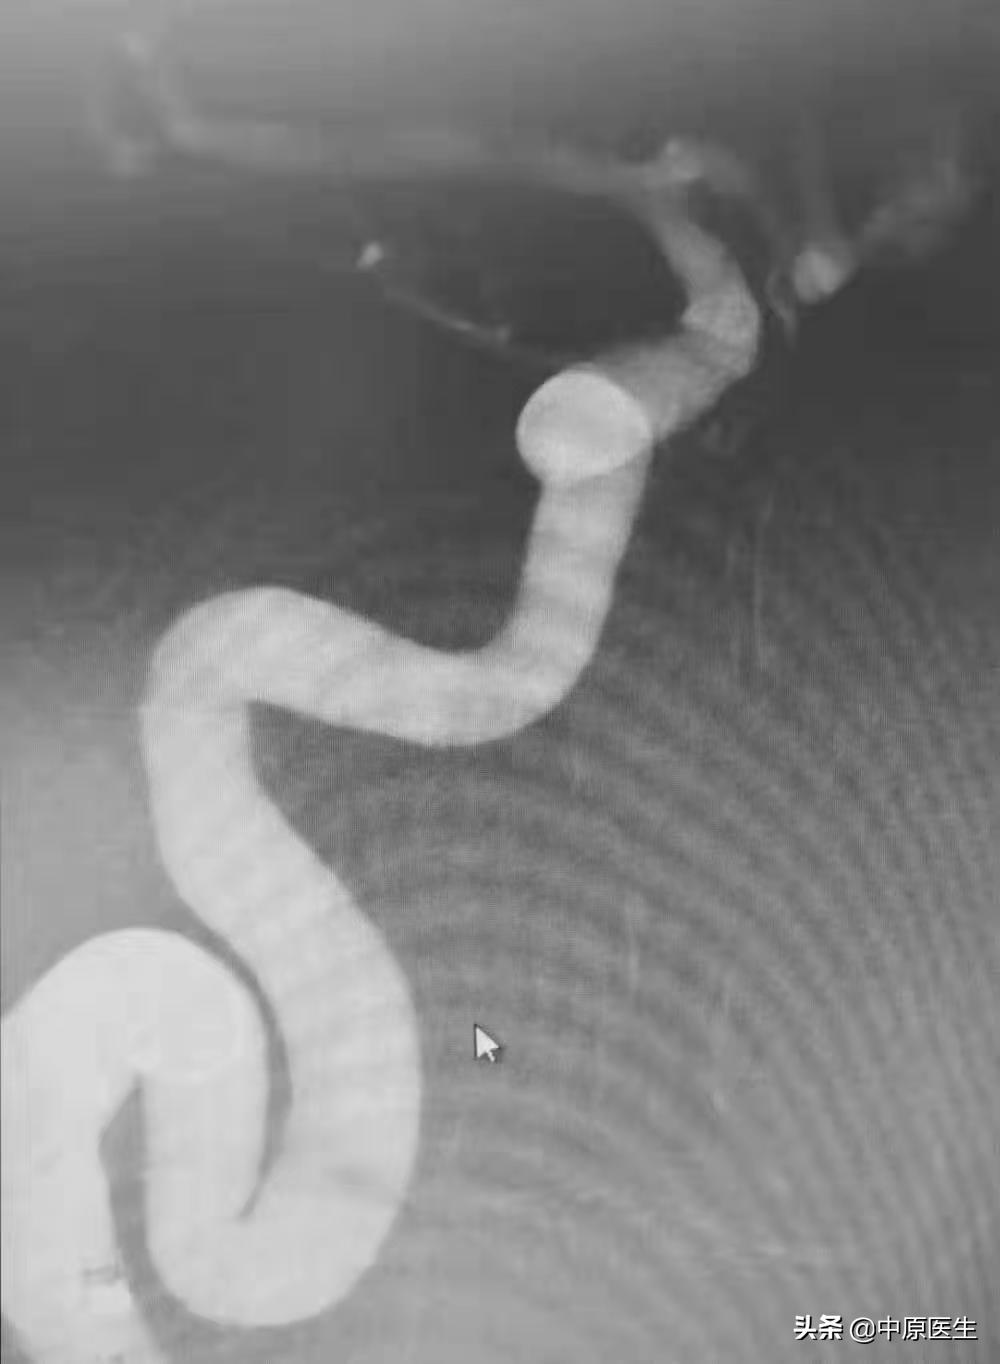

血管曲里拐弯儿,可把赵小源难为坏了。(见图2~6)

动脉瘤直径 3.8mm×4.2mm, 我建议第一个弹簧圈选择 6mm×15cm 的规格,可是 赵小源不听话,选了一个 6mm×20cm 的弹簧圈。(见图7~9)

结果,一个弹簧圈就把手术结束了。